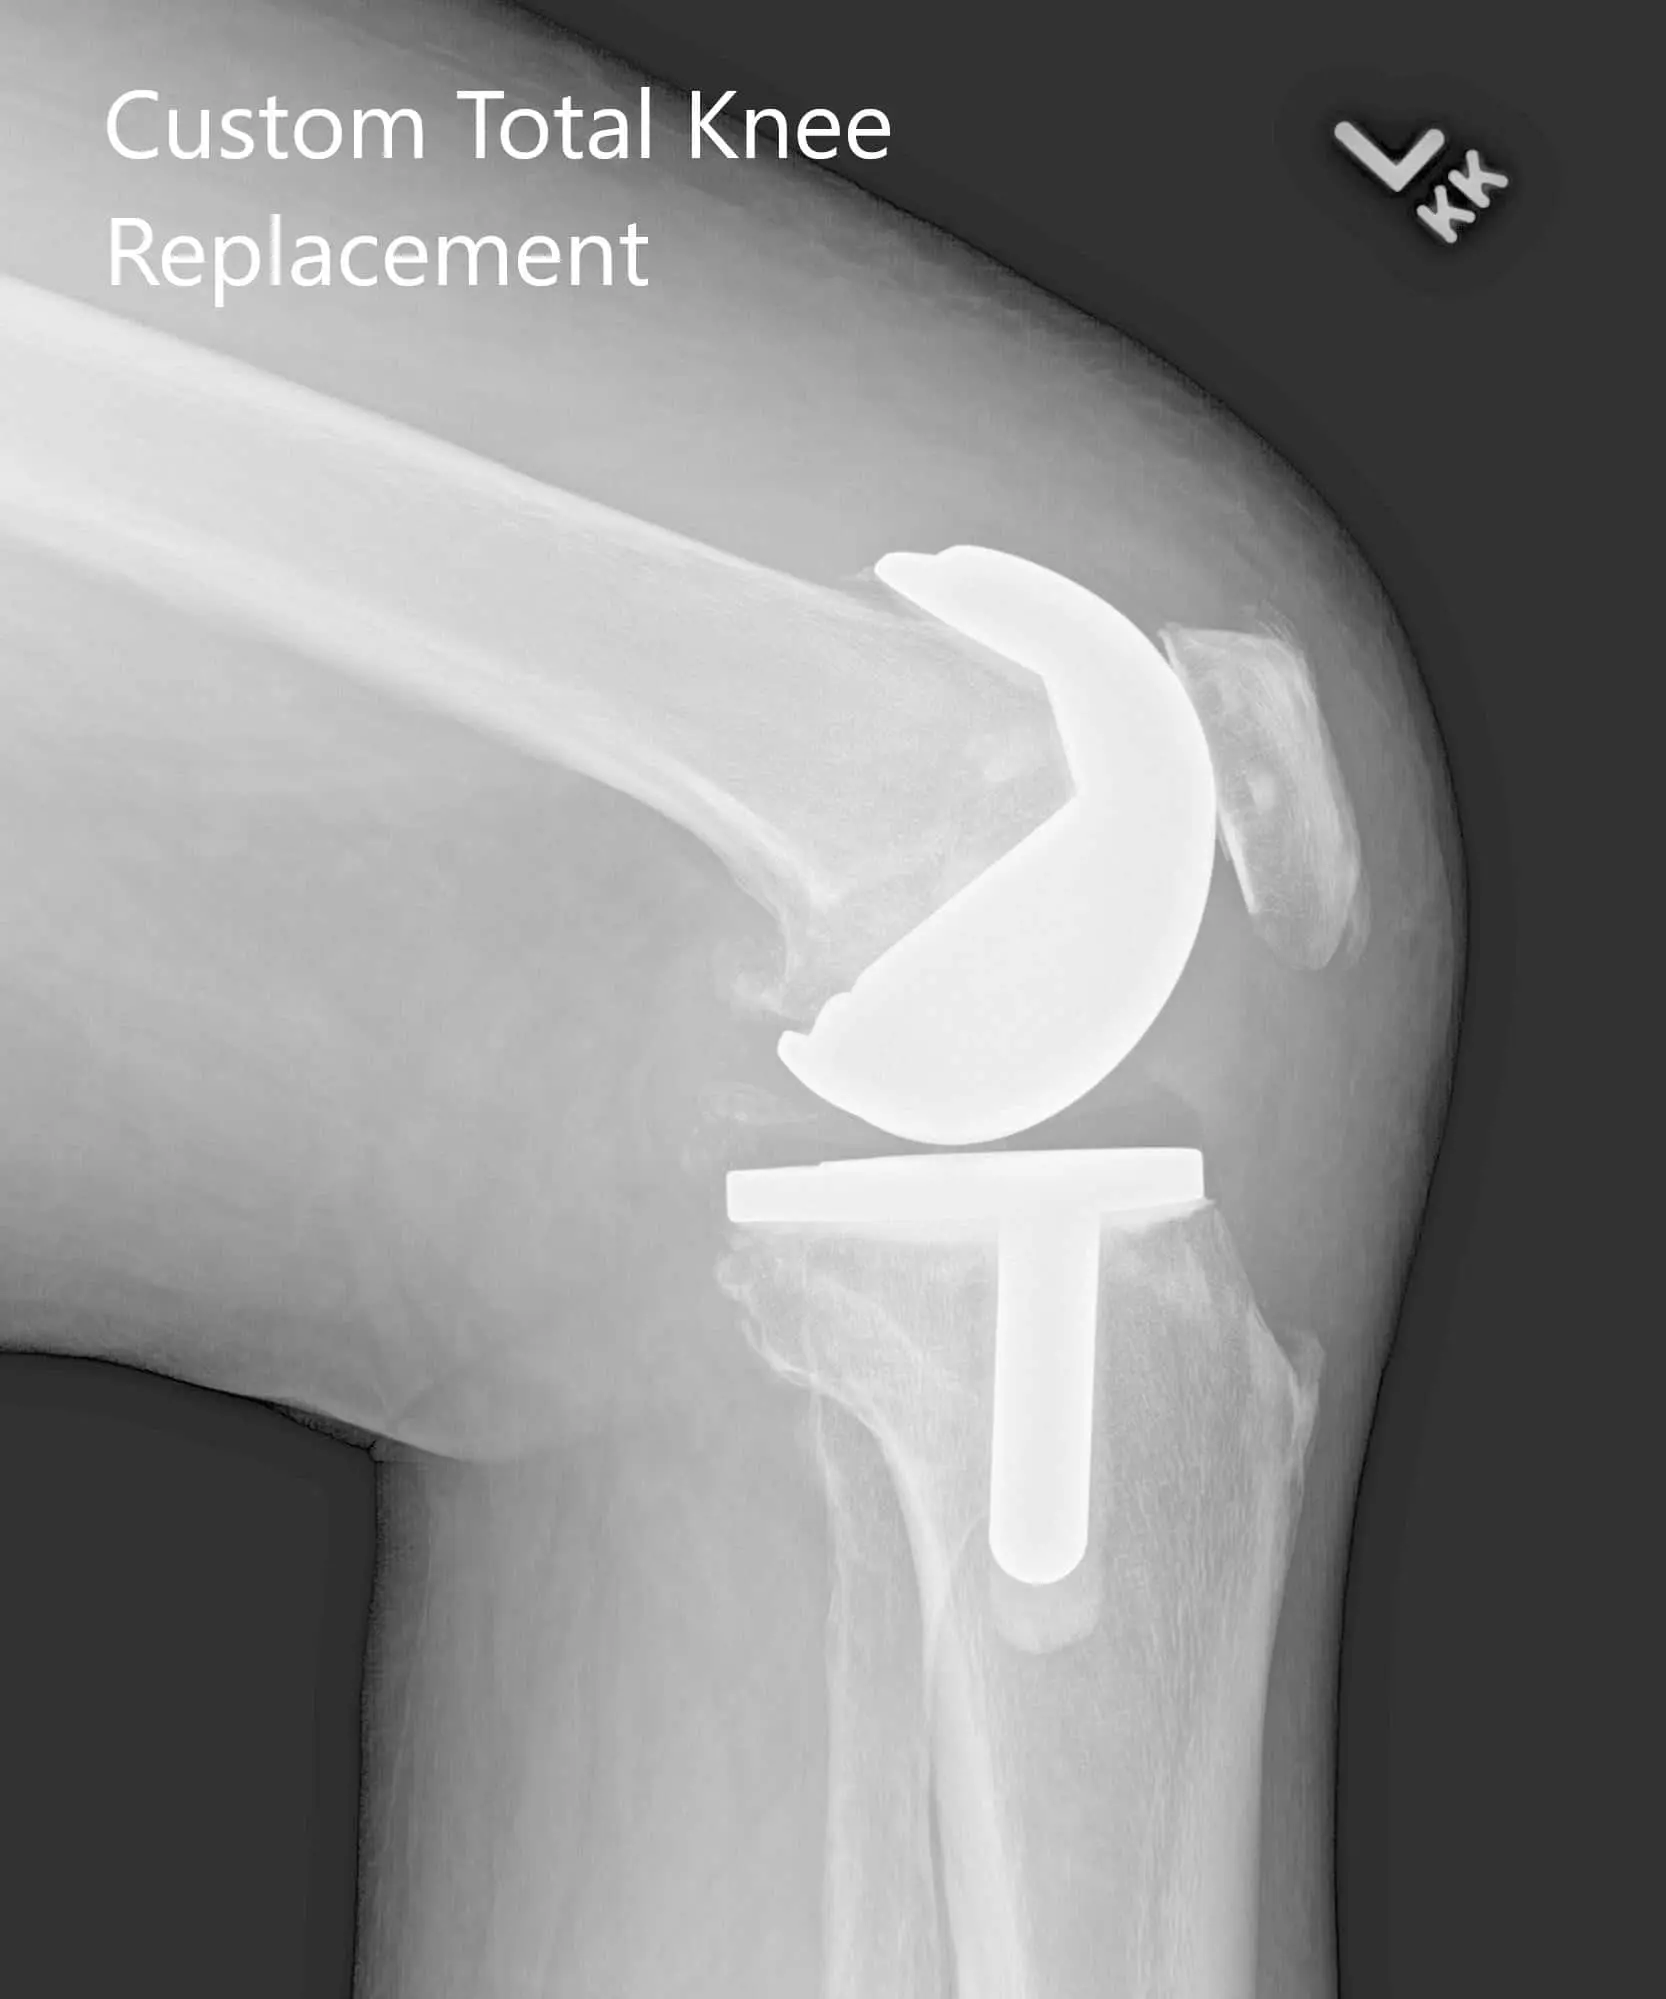

Postoperative X-ray showing AP and lateral images of the left kneePostoperative X-ray showing AP and lateral images of the left knee - img 2

Postoperative X-ray showing AP and lateral images of the left knee.